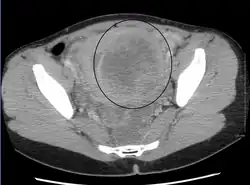

Multiple uterine leiomyoma

Sub-serosal uterine fibroid

Multiple uterine leiomyoma with calcification

Fibroids are monoclonal tumors and approximately 40–50% show karyotypically detectable chromosomal abnormalities. When multiple fibroids are present they frequently have unrelated genetic defects. Specific mutations of the MED12 protein have been noted in 70 percent of fibroids.[30]